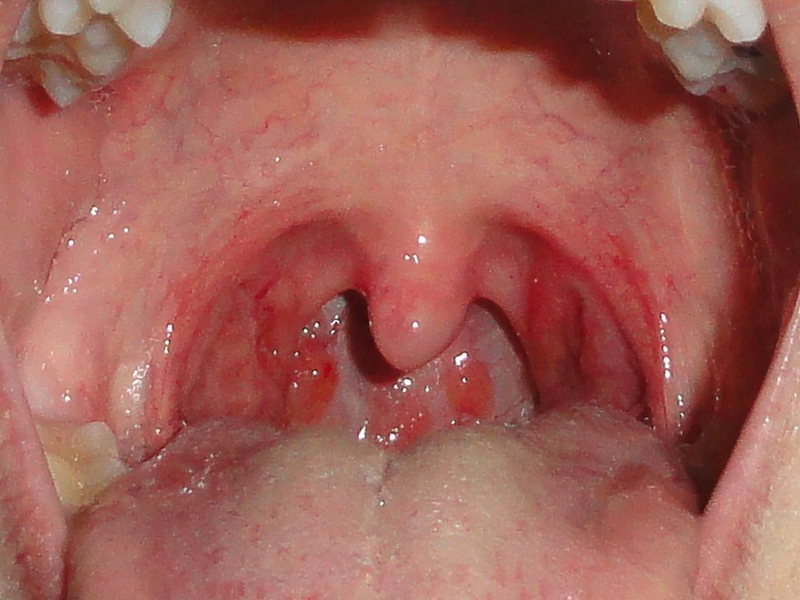

Cách xử trí viêm amidan cấp ở người lớn và trẻ em

Tình trạng viêm amidan cấp có thể khiến chúng ta vừa đau rát họng, vừa cảm thấy khó chịu, ảnh hưởng tới sinh hoạt hằng ngày. Nếu không điều trị dứt điểm bệnh còn có nguy cơ viêm nhiễm mãn tính, kèm theo đó là các biến chứng như lây lan viêm nhiễm sang những vùng lân cận, nhiễm khuẩn huyết… Vậy có cách nào để điều trị viêm amidan cấp ở người lớn và trẻ nhỏ, giúp ngăn ngừa bệnh tái phát không?

Viêm amidan cấp chính là tình trạng amidan khẩu cái bị viêm xung huyết dẫn tới đau rát, khó nuốt. Bệnh lý này có thể xuất hiện ở bất cứ lứa tuổi nào, từ viêm amidan cấp ở người lớn cho tới trẻ em. Nguyên nhân chính gây nên viêm amidan chính là vi khuẩn và virus. Kèm theo đó chính là các yếu tố thuận lợi như thời tiết thay đổi đột ngột, môi trường ô nhiễm, sức đề kháng kém…

Vị trí của amidan là nằm sau hầu họng, nơi có nhiều khe, hốc và là giao điểm giữa đường ăn với đường thở. Do đó, đây cũng là vị trí dễ tiếp xúc với các loại virus, vi khuẩn trong không khí, đồ ăn. Đó cũng là lý do mà amidan rất dễ viêm nhiễm. Trẻ nhỏ và trẻ vị thành niên từ 5 - 15 tuổi chính là nhóm thường mắc phải viêm amidan cấp nhất. Ngoài ra viêm amidan cấp ở người lớn cũng có khả năng xuất hiện.

Trường hợp nhiễm vi khuẩn phổ biến nhất là Streptococcus, xoắn khuẩn, tụ cầu, liên cầu… nằm khu trú trong niêm mạc họng hoặc xâm nhập từ bên ngoài. Bên cạnh đó viêm amidan cấp ở người lớn và trẻ nhỏ cũng có thể là do virus cúm, sởi, Herpes nữa. Ngoài ra nhóm đối tượng có tiền sử sâu răng, viêm lợi, viêm xoang thì còn có nguy cơ mắc viêm amidan cấp cao gấp nhiều lần bình thường.